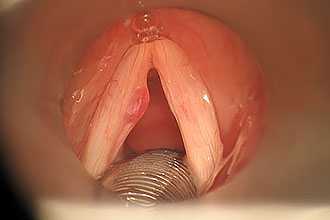

Диагностика проводится с помощью ларингоскопии, при которой специалист визуализирует покраснение, отечность связок, на поверхности которых отмечается мокрота. При гриппе на связках возможны кровоизлияния. Для определения инфекционного возбудителя проводится бактериологическое исследование, материал для которого собирается со слизистой ротоглотки. В анализах крови регистрируется лейкоцитоз.

При хронической форме при ларингоскопии наблюдается гиперпластический или атрофический тип болезни. У вокалистов, воспитателей и дикторов на поверхности утолщенных связок визуализируются узелки.

Проведение ларингоскопии — внешнего осмотра гортани и дыхательных путей зеркалом.

При необходимости используется ларингоскоп — эндоскопический прибор, позволяющий оценить отёк голосовых связок, скопление слизи, покраснение слизистой оболочки гортани и различные образования [17] [18] .